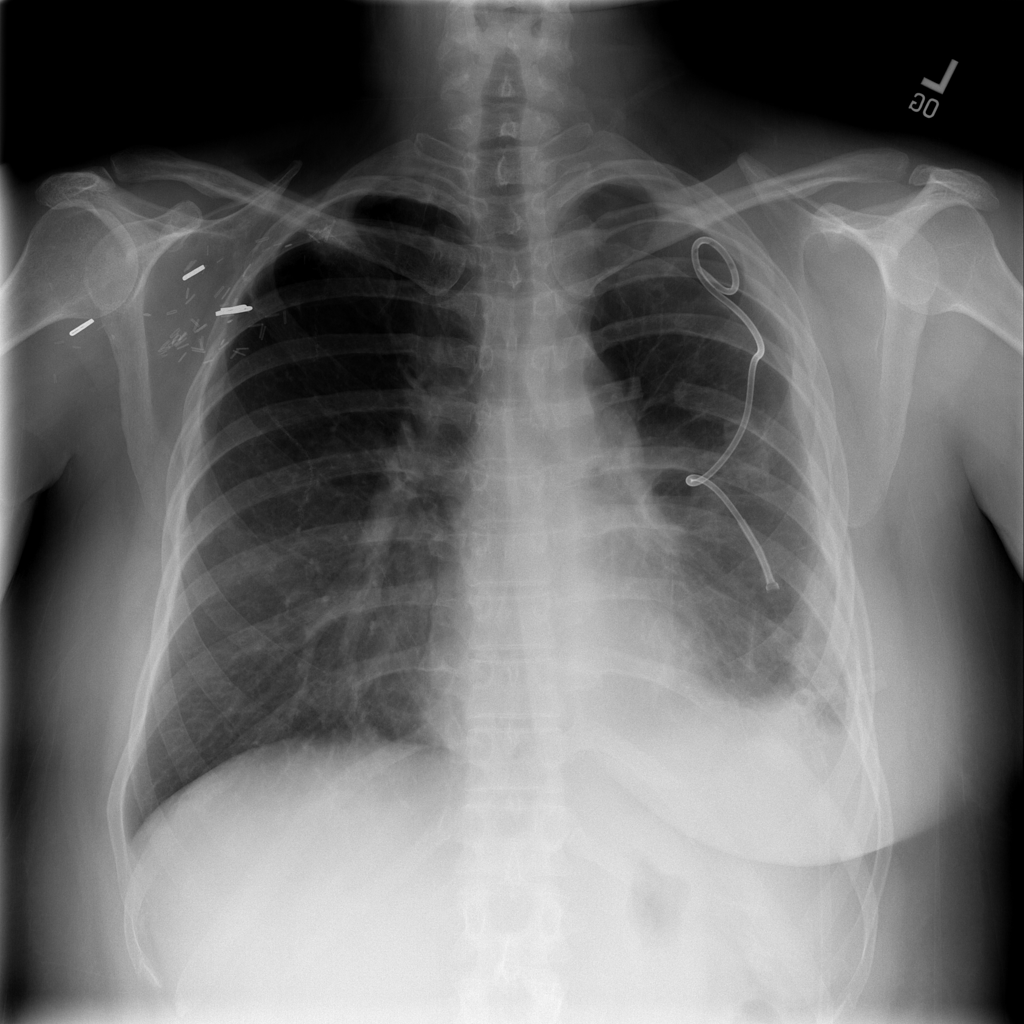

PAT-4639 · IMG-020Pneumothorax

PAT-4639 · IMG-020

PA